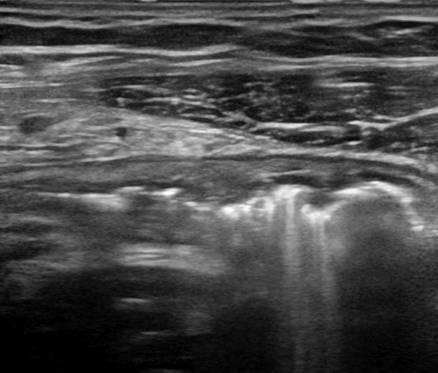

Viêm ruột

» Thông tin: Nữ giới – 18 tuổi.

» Lâm sàng: Tiêu chảy.